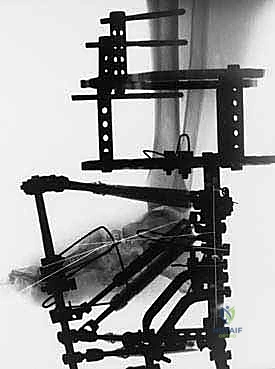

2. المرحلة الأولى: تطبيق جهاز التثبيت الخارجي (External Fixator Application)

- إدخال الأسلاك: يتم تمرير أسلاك معدنية رفيعة جداً وقوية (K-wires) ومسامير نصفية (Half-pins) عبر العظام في الساق والقدم بأماكن استراتيجية محددة مسبقاً بدقة لتجنب الأعصاب والأوعية الدموية، وذلك تحت توجيه الأشعة السينية المباشرة (C-arm) في غرفة العمليات.

- تجميع الإطار: يتم توصيل هذه الأسلاك بحلقات خارجية معدنية أو كربونية تحيط بالساق والقدم (إطار إليزاروف). يتم تثبيت هذه الحلقات معاً بواسطة دعامات قابلة للتعديل.

3. مرحلة التصحيح التدريجي (Gradual Correction Phase)

تبدأ هذه المرحلة بعد أيام قليلة من الجراحة. يقوم المريض (أو مرافقه) بتدوير صواميل معينة على دعامات الجهاز الخارجي بمقدار محدد جداً (عادة 1 مليمتر في اليوم).

5. مرحلة التصلب والشفاء (Consolidation Phase)

يبقى جهاز التثبيت الخارجي في مكانه لعدة أشهر (عادة من 3 إلى 6 أشهر) حتى تندمج العظام تماماً وتصبح قادرة على تحمل وزن الجسم. الميزة الكبرى هنا هي أن المريض يمكنه (بناءً على توجيهات الطبيب) البدء في تحميل الوزن جزئياً على القدم المصابة، لأن الإطار الخارجي هو الذي يتحمل العبء الميكانيكي وليس العظام الهشة.